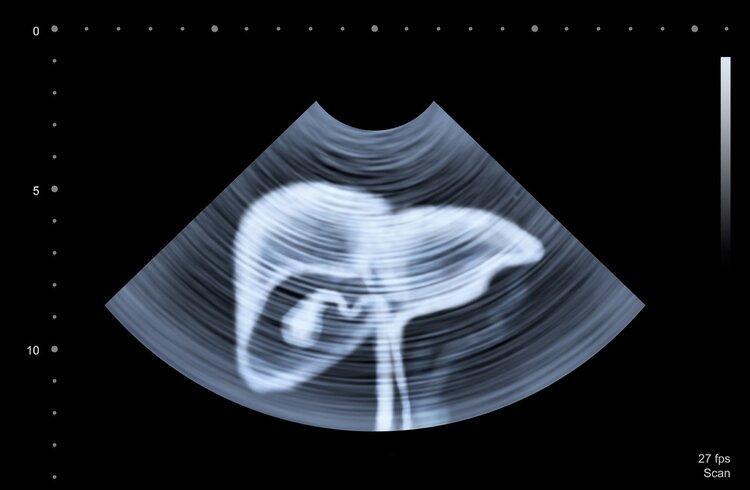

肝癌早期篩查手段主要是肝臟彩超、血清甲胎蛋白(AFP)檢查,年齡在40歲及以上,有肝硬化病史或HCV慢性感染的人屬於肝癌高危風險人羣,建議定期篩查。